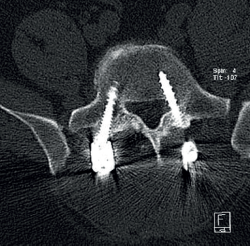

Cincuenta días tras el accidente se realizó fusión lumbar instrumentada L4-L5 con inserción de dispositivo intersomático por vía transforaminal derecha. En el segundo día postoperatorio presentó empeoramiento del dolor, objetivándose en la tomografía computarizada (Figura 2) malposición del tornillo L5 izquierdo que invadía el canal. Se reintervino a los 5 días corrigiendo el trayecto del tornillo. Sin embargo, persistió el dolor. La revaluación del caso, sumada a los hallazgos de EMG, motivó estudios complementarios de pierna y trayecto ciático (Figuras 3 y 4), detectándose una masa tumoral en el fémur izquierdo compatible con sarcoma fusocelular.

retla.08216.fs2508016-figura3.png

Figura 3. Radiografías del fémur izquierdo. A: proyección anteroposterior, con lesión ósea permeativa en la diáfisis femoral con reacción perióstica; B: proyección lateral, con irregularidad cortical y masa de las partes blandas adyacente, sugestiva de lesión tumoral.